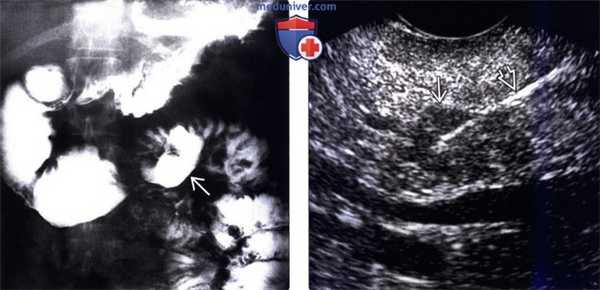

(Слева) На рентгенограмме визуализируется большая язва тощей кишки, которая (из-за спазма и отека) явилась причиной дилатации двенадцатиперстной кишки. Складки желудка утолщены; в результате усиления секреции бариевая взвесь в просвете желудка разбавлена и недостаточно хорошо покрывает слизистую оболочку. Эти изменения при рентгеноскопии являются типичными для СЗЭ.

(Справа) При эндоскопической ультрасонографии у этого же пациента определяется объемное образование, также визуализируется игла, при помощи которой была произведена биопсия образования во время процедуры. Была подтверждена гастринома, наличием которой и была обусловлена симптоматика, имеющаяся у пациента.